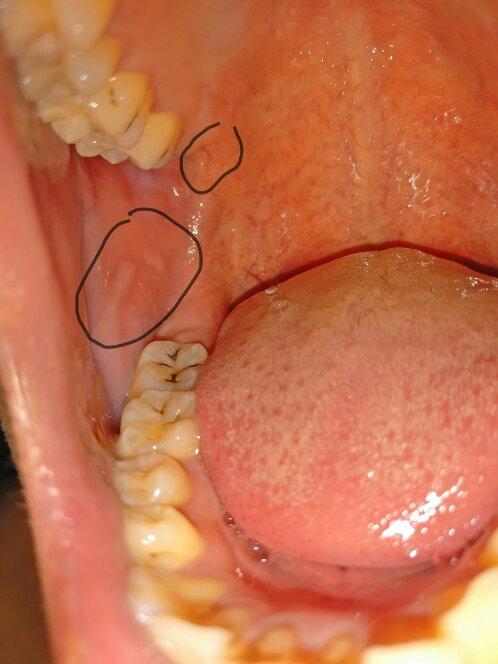

上嘴唇皮脂腺异位实图

上嘴唇皮脂腺异位实图,上嘴唇皮脂腺异位

上嘴唇的白色小点不痛不痒,百度查了一下是皮脂腺异位症,有同样困扰

图一是皮脂腺异位

口腔内有时候长小疙瘩,嘴唇是疱疹还皮脂腺异位症